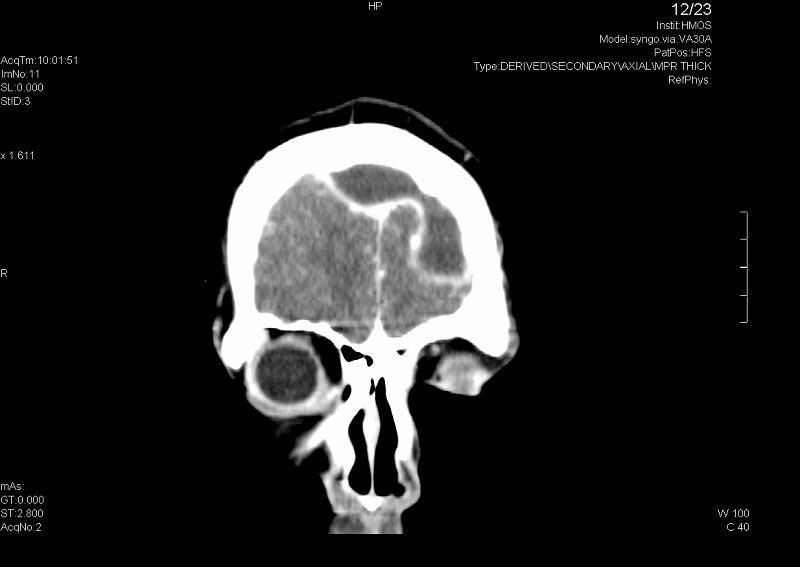

Ante los hallazgos del fondo de ojo se decide realizar una tomografía computarizada (TC) craneal, que es compatible con sinusitis en senos paranasales izquierdos frontal, maxilar y celdillas etmoidales anteriores-medias complicada con absceso epidural anterior bifrontal (de 6 × 2 cm) y solución de continuidad/dehiscencia milimétrica en pared posterior de seno frontal izquierdo.